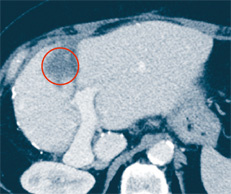

Abb. 2c

Ergebnis nach erfolgreicher Ablation: Die Metastase ist zerstört. Der Kreis zeigt das Areal, in dem sich die Metastase vormals befand und das mit einem erforderlichen Sicherheitsabstand therapiert wurde.